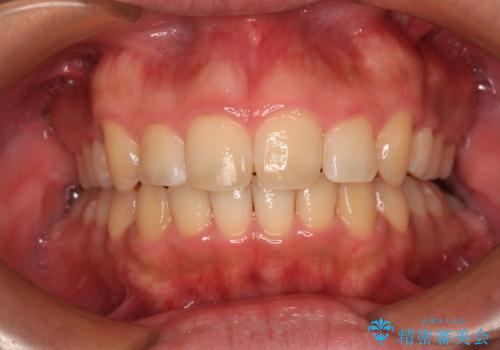

開咬を治す インビザラインによる矯正治療

- 上下前歯の開咬を気にして来院された患者様です。

途中1年8ヶ月ほど来院されず、久しぶりの来院後は治療が面倒とのことで、前歯の叢生や隙間に不十分な点が残った状態での終了となりました。